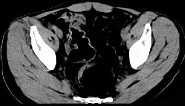

- 单项选择题女,51岁, 腹胀、腹痛、进行性消瘦,影像检查如下图, 最佳诊断是 ( )

A、乙状结肠Crohn病

B、乙状结肠结核

C、乙状结肠癌

D、乙状结肠淋巴瘤

E、乙状结肠息肉